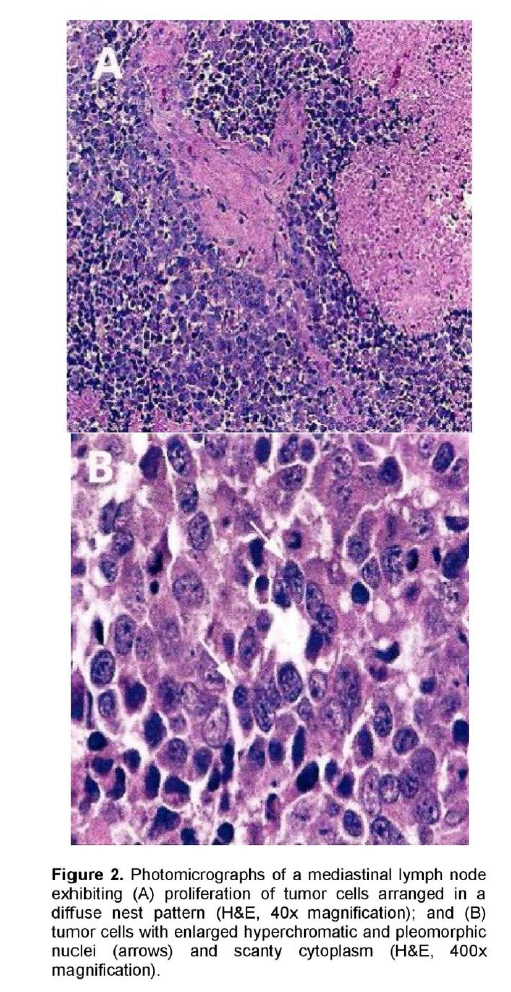

A 72-year-old male, previous smoker presented with cough and shortness of breath of one week duration. His chest x-ray showed linear densities in the right paracardiac and both lung bases. Contrast-enhanced CT scan uncovered multiple, enlarged soft tissue masses in the pretracheal, right paratracheal, subcarinal and right paravertebral regions (Figure 1). There were also reticular ground glass opacities scattered in both lung bases and periphery. No endobronchial mass was seen. The thyroid, adrenal glands, pancreas, liver and the rest of the visceral organs were normal. Mediastinoscopy with excision biopsy was done. Microscopic examination revealed large tumor cells arranged in solid sheets or nests (Figure 2). The differential diagnosis included diffuse large cell lymphoma and poorly-differentiated carcinoma believed to be primary lung versus mediastinal cancer. Positive immunohistochemical staining of tumor cell cytoplasm for Chromogranin, Synaptophysin, and CD 56 (Figure 3), and negative for cytokeratins confirmed the diagnosis of Large Cell Neuroendocrine carcinoma. Whole body [18F]-Fluorodeoxyglucose (FDG) PET-CT scan was done to locate the primary tumor and delineate the extent of disease.

Figure 2. Photomicrographs of a mediastinal lymph node exhibiting (A) proliferation of tumor cells arranged in a diffuse nest pattern (H&E, 40x magnification); and (B) tumor cells with enlarged hyperchromatic and pleomorphic nuclei (arrows) and scanty cytoplasm (H&E, 400x magnification).